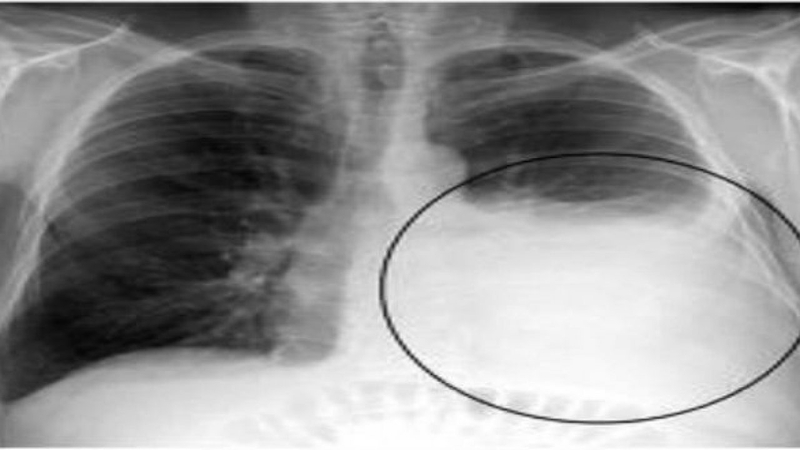

Một nguyên nhân khác gây ra khó thở và mệt mỏi là sự tích tụ chất lỏng trong màng phổi. Khi có sự tích tụ chất dịch trong màng phổi, người bệnh cảm thấy mệt mỏi khó thở, đặc biệt khi nằm xuống.

Ngoài ra, người bệnh có thể trải qua đau tức ngực ở phía màng phổi bị tràn dịch, ho khan hoặc có đờm, cơ thể yếu đuối và mệt mỏi kéo dài.